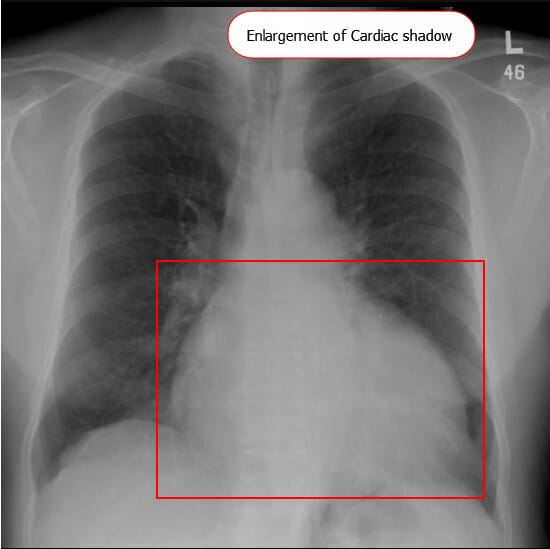

Dilated Cardiomyopathy (DCMP)는 심장이 확장되고 수축 기능이 떨어져 심부전과 부정맥을 유발하는 질환입니다. 쉽게 말하면, 심장 근육이 약해지고 늘어나서 충분히 피를 내보내지 못하는 상태입니다.

DCMP : 심실이 확장되고 심근 수축력이 저하되어, 심박출량 감소 및 혈액 순환 장애를 초래하는 심장 질환입니다.

| ✅ 좌심실 또는 양심실이 확장되고 수축력이 감소하여 심부전, 부정맥, 혈전 형성 위험이 증가하는 상태입니다. |

2. 심장초음파(Echocardiography) 소견

- 좌심실의 확장이 관찰됨.

| 좌심실 확장(Left ventricular dilation) |

| 좌심실 크기가 비정상적으로 커지고 벽 두께는 상대적으로 얇아짐 |

| 좌심실 수축 기능 저하(Decreased LVEF) |

| 좌심실 구혈률(EF)이 40% 이하로 감소 |